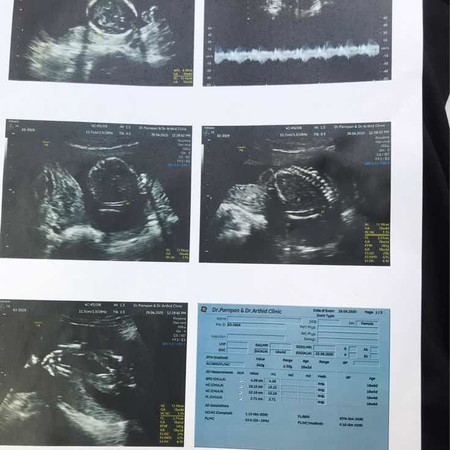

18w4d ?

คุณหมอบอกว่า ผู้หญิง มีใครดูออกไหมค่ะ คุณแม่ดูไม่ออกเลย. ???

ลูกสาวตามหมอบอกเลยค่ะแม่ ลูกชายจู๋จะโผล่ชัดเลยจ้า

ที่หว่างขาจะเห็นเส้นขีดๆคล้ายแซนวิส หญิงค่ะ

มาเป็นกลีบเลยค่ะแม่ ยินดีด้วยนะคะ ☺️